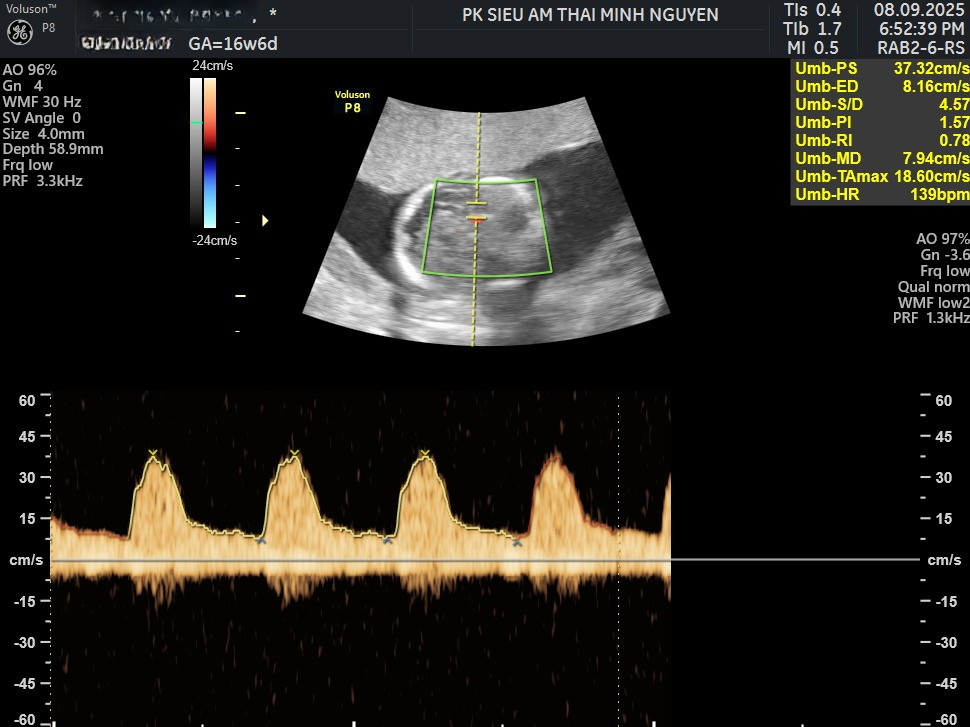

Cũng có hiểu sai khác. Người ta thấy nghi ngờ trên siêu âm và coi như đã chẩn đoán chắc chắn. Siêu âm chỉ cho hình ảnh và mức ảnh hưởng. Siêu âm không cho mẫu máu thai. Vì vậy, nghi ngờ thiếu máu trên siêu âm vẫn là nghi ngờ. Với thai nhi bị thiếu máu di truyền, bước xác định thường là đo trực tiếp chỉ số máu thai khi có chỉ định.

Nghi ngờ trên siêu âm có chắc chắn không

Không nên kết luận chắc khi chỉ có hình ảnh. Siêu âm cho thấy hệ quả lên tim và dịch trong cơ thể thai. Siêu âm không đo trực tiếp huyết sắc tố của thai. Với Thai nhi bị thiếu máu di truyền, xác định mức thiếu máu thường cần đo chỉ số máu thai trong các tình huống nguy cơ vừa đến cao.

Lấy máu cuống rốn để chẩn đoán và tiên lượng trong thai kỳ

Lấy máu cuống rốn là thủ thuật lấy mẫu máu thai từ tĩnh mạch rốn dưới hướng dẫn siêu âm. Mục tiêu là đo trực tiếp nồng độ huyết sắc tố hoặc thể tích khối hồng cầu. Kết quả giúp phân tầng mức độ thiếu máu. Từ đó mới quyết định theo dõi hay truyền máu trong tử cung.

Tiên lượng không chỉ dựa vào một con số. Bác sĩ thường nhìn thêm dấu phù thai. Bác sĩ nhìn chức năng tim thai. Bác sĩ nhìn có tràn dịch không. Bác sĩ nhìn tuổi thai hiện tại, càng được đánh giá sớm, kế hoạch càng rõ.